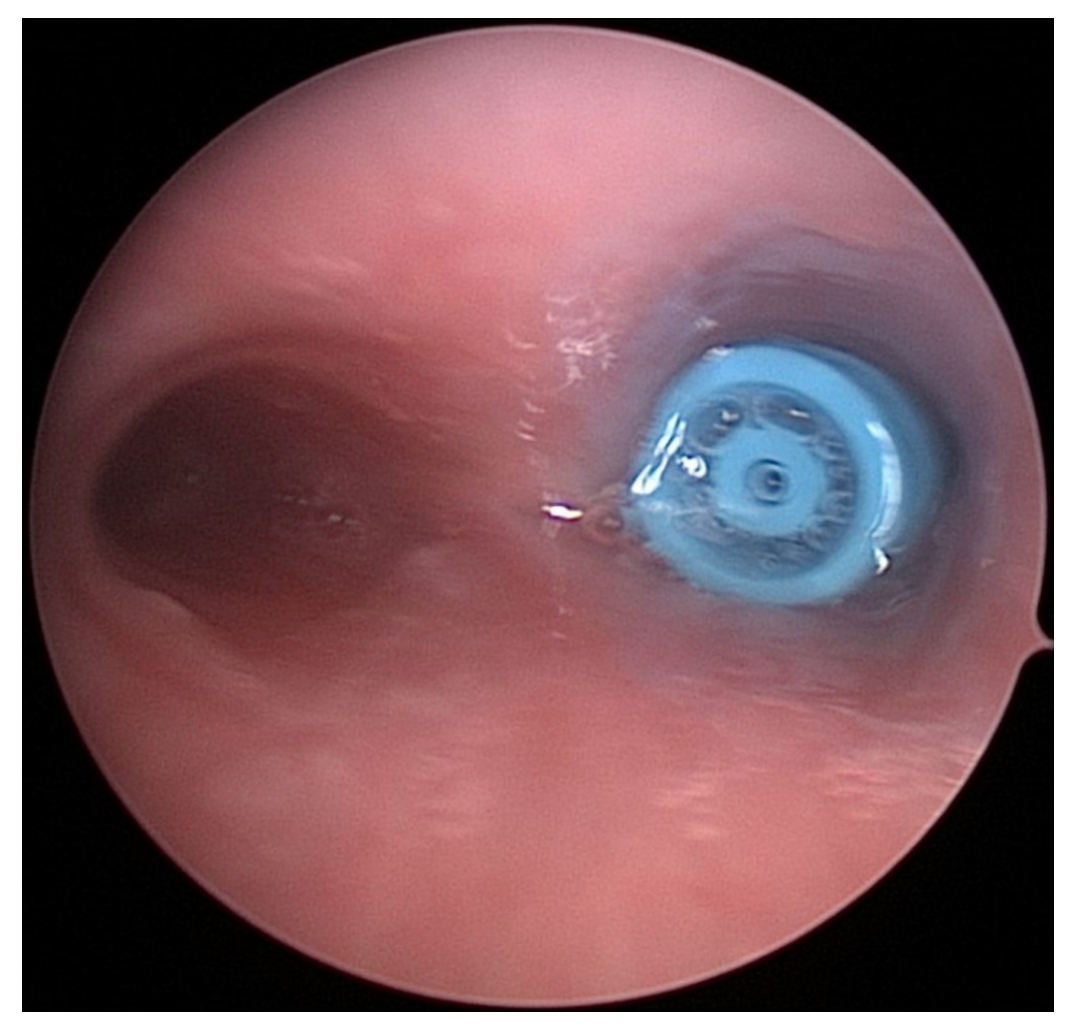

1. CT confirms a metallic object traversing the patient’s supraglottic airway with partial embedment into the vallecula. After receiving ketamine, the patient undergoes evaluation with Glidescope video laryngoscopy, and the foreign body is retrieved via Alligator forceps (Figure 9). After foreign body removal, the patient was discharged home with no complications.